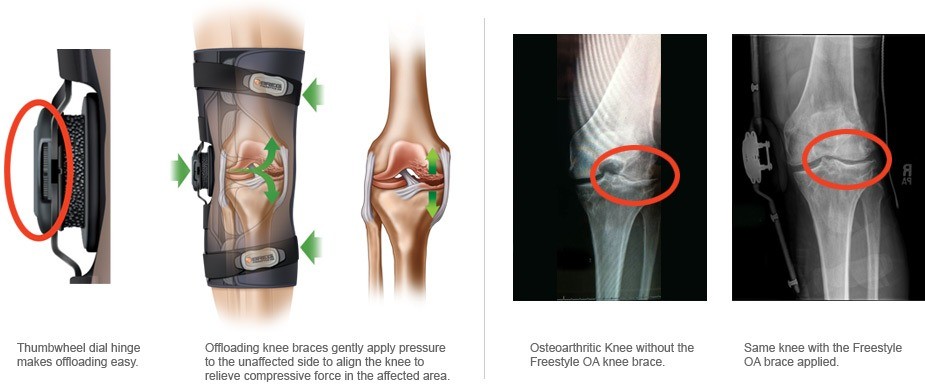

For those with knee OA, knee braces can be a game-changer. They are designed to offload the pressure from the part of the knee affected by arthritis, which can significantly reduce pain and improve mobility. By redistributing the weight and stress on the knee joint, braces can allow individuals to continue participating in their favorite activities with less pain.

As we delve into the world of assistive devices for OA, let’s highlight the Freestyle OA knee brace. This brace is specifically designed for people dealing with OA in the knee. It’s a supportive brace that focuses on improving the quality of life for individuals with knee pain due to OA. Here’s how it stands out:

- Targeted Relief: It’s designed to offload the affected compartment of the knee, reducing the stress and thereby the pain.